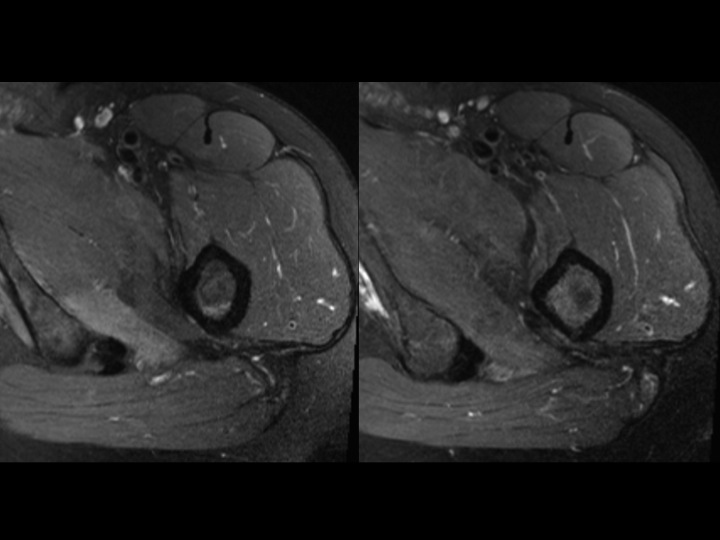

36M with DDH, chronic pain, recent onset more severe pain

I am asking for your thoughts. This is chronic DDH with severe secondary DJD. The femoral head is superiorly migrated with chronic degenerative remodeling of the FH and acetabulum. This brings the posteroinferior acetabular rim and lesser troch into close approximation and appears to cause some sort of impingement. Caudal to that site, there is isolated edema of what is either the Quad Femoris or possibly the Add Magnus (I am confused by the anatomic distortion), which cannot be due to direct muscle friction. I do not know if the Acetabular-Less Troch friction is the direct cause of symptoms, if that is causing nerve impingement, or if there is a muscle strain due to the abnormal stress of the deformity (seems least likely as the deformity is chronic). Please help.

acetabular-femoral impingement